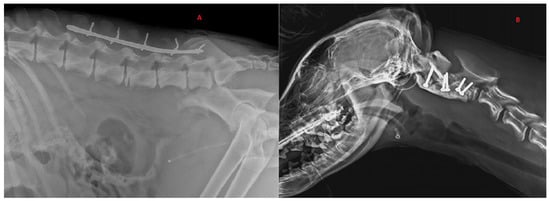

Figure 3.

Radiographic exams. (A) Application of dorsal spinal staple in 50-month-old, male, Italian wolf with L5 vertebral fracture. Bilateral ileal: body oblique fractures; (B) application of ventral implant with screw–PMMA in 7-month-old, female, Italian wolf with C2 vertebral fracture and luxation.

Six wolves (42.9%) were treated surgically. Preoperative neurological status was grade 3 in four wolves and grade 4 in two wolves. Two (33.4%) of six cases were stabilized using screws and polymethylmethacrylate (PMMA) implants, while the remaining cases (66.6%) were stabilized using dorsal spinal stapling. For the spinal stapling, a Steinmann pin was contoured to act as a staple around spinous processes spanning to the site of injury. The size of the Steinmann pin was variable according to the size of the patient. Where possible, three vertebrae cranial and caudal to the injury were included in the staple. The fixation of the pin was achieved by drilling small holes through the base of the spinous processes. Loops of cerclage were then threaded in each hole and tightened around the pin. For the wolf with an L3 fracture, 3.5 mm cortical screws were used, and the angle of insertion and reference points were chosen according to the CT results. Fixation was performed unilaterally, using two screws on the fractured vertebra, two on the cranial one and two on the caudal one. Reduction forceps were used to maintain the unstable intervertebral articulation in a proper position while PMMA was applied and hardened. During curing of the PMMA, the surgical site was flushed with sterile 0.9% saline to decrease thermal injury to the surrounding soft tissues. Only one wolf presented with a cervical fracture of the vertebral body of C2, which was treated with 2 mm cortical screws (two transarticular screws between C1 and C2, two screws on the transverse body of C2) all encased in a reinforcement of PMMA. None of the patients required surgical access to the spinal cord for spinal decompression during spinal fixation. Four of the wolves who underwent SFL stabilization had concurrent orthopedic injuries. These fractures were surgically addressed during a second anesthesia because spinal stabilization was prioritized as an emergency treatment. Post-operative care and analgesia were adapted according to the neurological and clinical status of each patient. For long-term analgesia, tramadol (4 mg/kg t.i.d.) was administered orally for 10 days. In addition, all wolves received antibiotic therapy with oralcefadroxil (Cefa-Cure Tabs, MSD, Segrate 20090, Italy) (20 mg/kg orally s.i.d.) for 10 days and an anti-inflammatory course of prednisolone (Prednicortone, Dechra, Zuiveringweg 8243, Holland) starting from 0.5 mg/kg s.i.d. for the first 7 days and tapering gradually over the next 7 days.